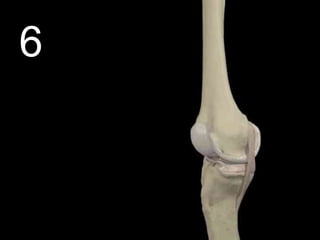

 A human joint: A place where two bones

meet.

• Joints can be…

– A.) Fibrous (immoveable)

– B.) Cartilaginous (partially moveable)

– C.) Synovial (freely moveable)

 Hinge Joint: Allows extension and retraction.

Copyright © 2010 Ryan P. Murphy